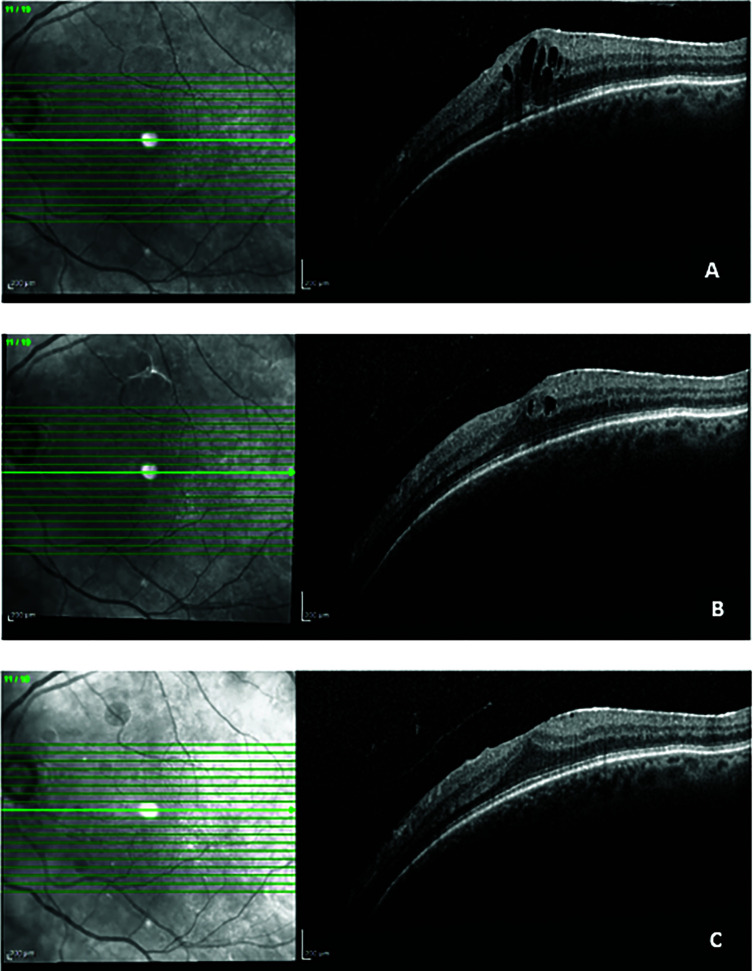

This is a collection of clinical experiences exploring the real-world effectiveness of a hydrophilic curcumin-based oral formulation (CHC, Diabec®) in the management of macular oedema across diverse retinal conditions, including diabetic macular oedema, central serous chorioretinopathy, branch retinal vein occlusion and Irvine-Gass syndrome. Eight cases reported significant improvements in best-corrected visual acuity and central macular thickness, with complete resolution of oedema in some instances. CHC was well tolerated, with no adverse effects reported. These findings suggest that CHC is a safe and effective adjunct or standalone therapy for chronic or refractory macular oedema, enhancing anatomical and functional outcomes in real-world settings.